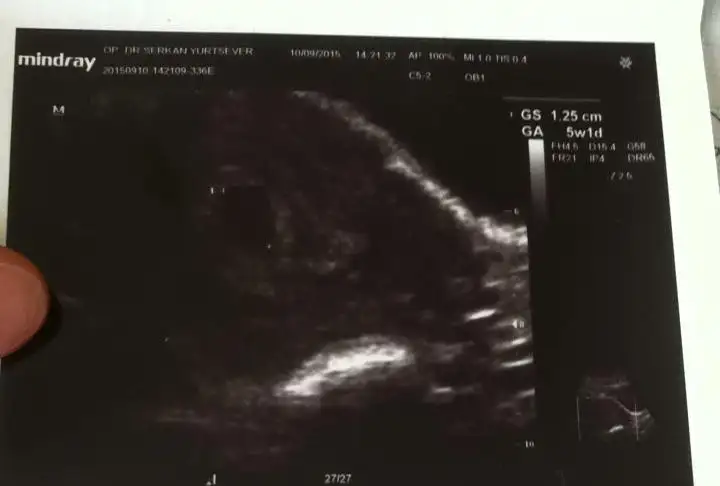

Benim de sizinle tarihlerimiz aynı Bizde kesemizi gördük ayın 18 inde çağırdı tekrar ama benim ultrasonda sata göre daha küçük çıkıyo kese sizin durumlar ne?

Kaç haftalık olduğunu sordum araya başka konular girince söylemedi doktorum ama kağıttan kese boyutu olarak 6 mm yazıyor güzel dedi Dr. .23 ünde gidecez biz de inşallah bebeklerimizi görürüz